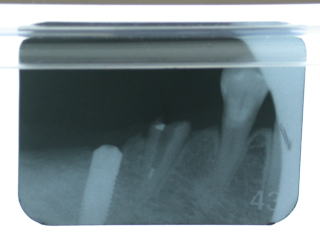

右下6番欠損です。

植立後約半年間、しっかりと固定するまでの待機期間中に手前右下5番のメタルボンドが外れてしまいました。

ヒーリングアバットメント装着。